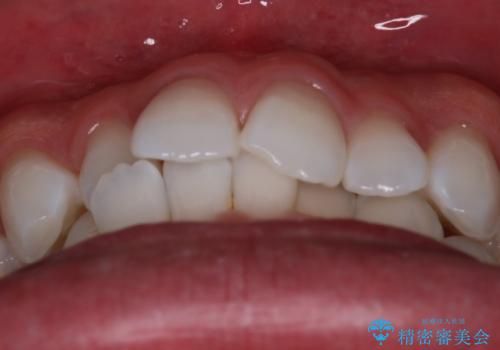

- がたつきが気になるとの事で来院されました。

目立たない装置で費用も抑えたいとの希望があったため、インビザラインにて治療をすることとなりました。

上下顎ともにIPR(歯と歯の間を削る処置)を行い歯並びを整える治療計画を立てました。